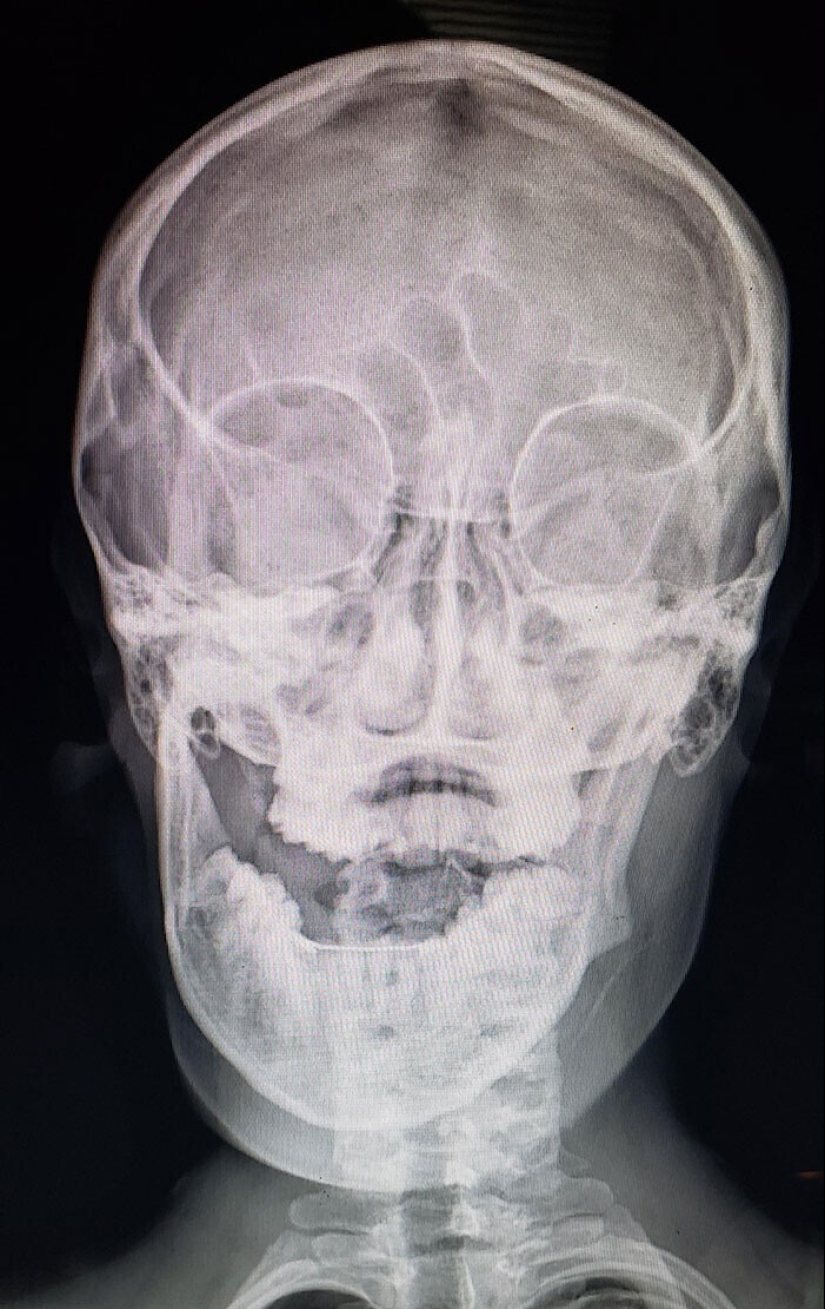

La artritis reumatoide